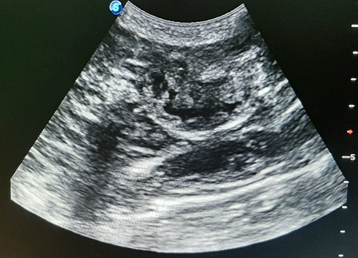

Canine pyometra is one of the most frequent reproductive organ disorders in reported in intact female dogs, particularly during the diestrus phase of estrus cycle and progesterone dominant uterus.1 Pyometra is accumulation of exudates within the uterine lumen, typically occurring during or immediately after a period of progesterone dominance. Clinical signs associated with this kind of disorder include lethargy, anorexia, polydipsia, polyuria, vomiting and unusual vaginal discharge (Kuplulu et al., 2009).2 The most accurate method of diagnosing pyometra in canines is ultrasonography.3 Both qualitative and quantitative examination is possible in diagnosing pyometra.4 In case of Pyometra, uterus will appear as distended and anechoic sacs are visualized due to pus accumulation. The advantage of ultrasonography is that it can detect the intrauterine fluid even in smaller quantity and also detect the abnormal changes in the ovaries and uterine tissue.5 Depending on the extent of uterine involvement, ultrasonographic features of pyometra may vary, the areas of uterine involvement may appear as hypoechoic or anechoic areas like if moderate involvement is there, it will appear as hypoechoic, roughly round structure ventral to ventro-lateral to the anechoic urinary bladder in transverse section. On ultrasound examination, cystic endometrial hyperplasia (CEH), which precedes pyometra, appear as small, cyst like fluid-filled regions within the endometrium (Figure 1). Similarly, transabdominal ultrasonography is effective way in diagnosing closed type of pyometra. A characteristic multiple anechoic sacculations with changes in the uterine wall thickness is visible as depicted in Figures 2–4. Therefore, ultrasound can be used as non-invasive and rapid diagnostic technique to detect the uterine pathologies like CEH and pyometra.6–10

Figure 1 Ultrasonographic view of uterus showing cystic enlargement of endometrium (CEH-Pyometra complex).